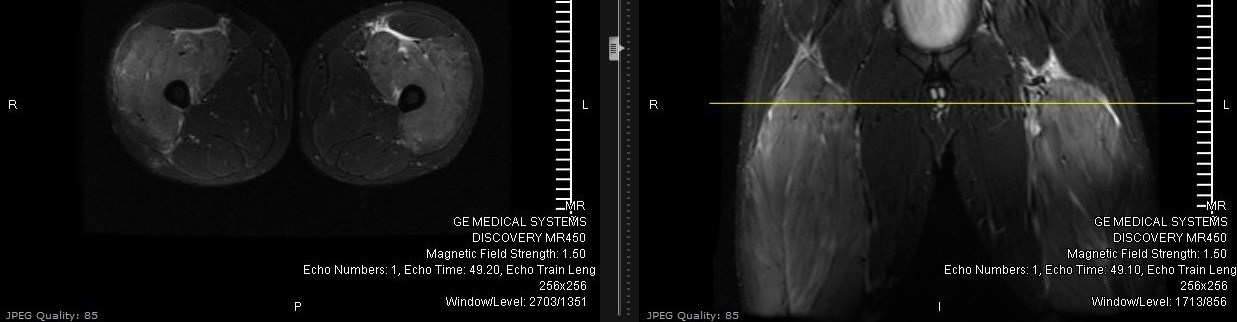

Vitals are within normal limits. On exam, the patient’s anterior thighs are hard, swollen, and tender to touch and have limited passive and active range of motion. Sensation and capillary refill are normal in the distal lower extremities. Serum creatine kinase levels are 41,000; other labs include: BUN 14, Creatinine 0.73, Potassium 4.4, Phosphorus 3.8, Calcium 8.8. Urine dipstick is positive for blood, though no RBCs are seen on microscopy. MRI imaging shows edema and inflammation of the anterior compartment of the thighs, with patent blood vessels and no evidence of nerve damage (see image 1).

| Image 1 |